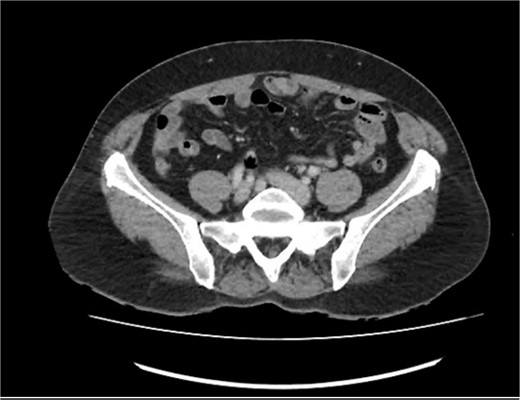

A 56-year-old female presented to her general practitioner with chronic intermittent RIF for months. She was otherwise well with no systemic symptoms. Regular medications included meloxicam 15 mg daily. Previous surgical history was significant for left oophorectomy for a dermoid cyst and total hysterectomy. They had no previous colonoscopies or gastroscopies and no family history of colorectal cancer. On initial examination, she appeared well with vital signs within normal range and exhibited RIF tenderness to deep palpation. Laboratory tests demonstrated normal white cells and liver function test. A pelvic ultrasound demonstrated a mildly prominent appendix 10 mm in diameter close to the anterior wall where the patient was tender. The distal tip of the appendix demonstrated a small echogenic region of 8x5mm which was thought to demonstrate collapse or debris. There was adjacent echogenic fat and three hypoechoic rounded lymph nodes, the largest measuring 12 mm. An outpatient computer tomography (CT) abdominal/pelvis with intravenous contrast was performed 4 days following this, demonstrating a mildly thickened appendix with a maximum diameter of 11 mm with mild mucosal enhancement, no fat stranding and a small appendiceal diverticula. The peri appendiceal fat plane also appeared normal, as demonstrated in Fig. 1.

CT abdomen/pelvis in axial view, demonstrating a mildly thickened appendix and a small appendiceal diverticulum.